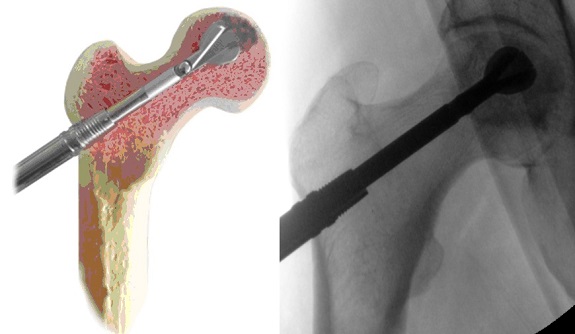

I primo tempo chirurgico consiste nel prelievo di midollo osseo da cresta iliaca. Il sangue midollare prelevato viene trasferito in un apposito centrifuga a doppia camera che verrà azionata al fine di separare il plasma dagli elementi cellulari.

Il secondo tempo chirurgico è la procedura di core decompression con strumentario innovativo per la bonifica tridimensionale della lesione. Si esegue una piccola incisione di circa 1 cm distale al trocantere.

Sotto controllo scopico si infigge il filo di K attraverso il collo femorale fino all’area di necrosi.

Viene quindi eseguito un carotaggio di 9 mm di diametro e tramite tale accesso viene inserita una fresa manuale con una punta espandibile distale per rimuovere la lesione tridimensionale.

Infine il canale viene zaffato con un osso omologo arricchito dal concentrato cellulare midollare e PRF autologo preparato il giorno precedente l’intervento presso l’ematologia dell’istituto.